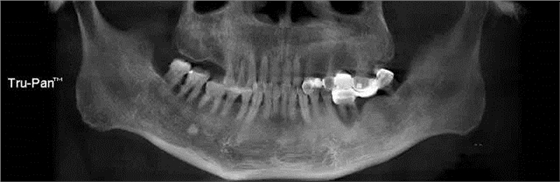

第一圖、臨床上最常見的上頜竇類型之一(高度稍顯不足、上頜竇內(nèi)干凈,提示做上頜竇內(nèi)提升即可)